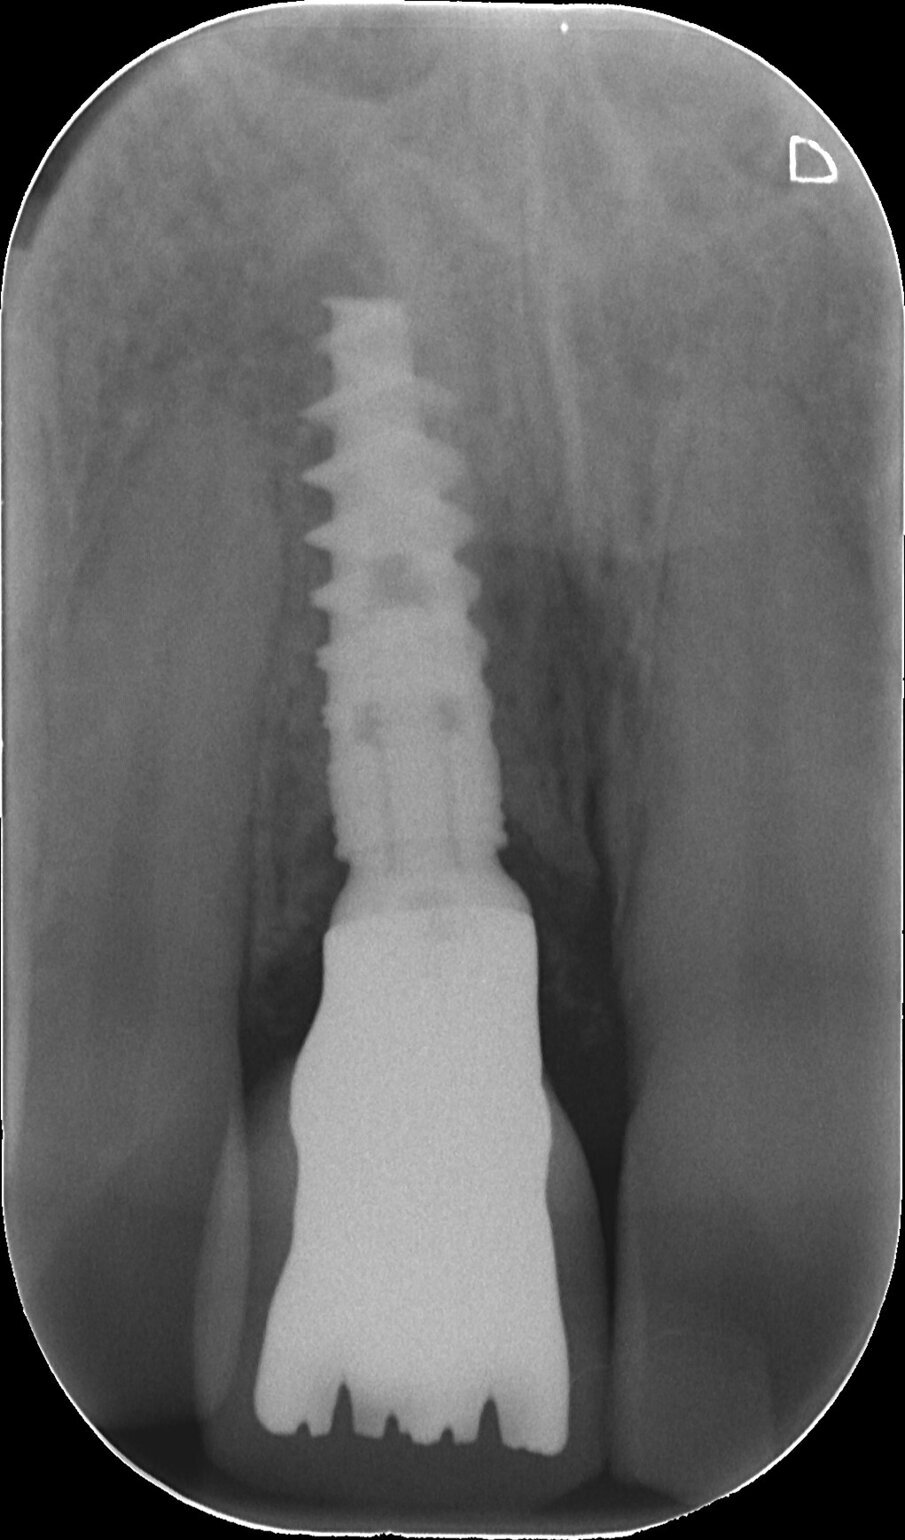

Una paziente di 34 anni di età si è presentata alla nostra osservazione lamentando la mobilità e il colore giallognolo dell’incisivo centrale superiore di destra. Effettivamente, all’esame radiografico era evidente anche un accentuato riassorbimento della radice e si decise così di programmare un impianto post-estrattivo immediato con contestuale inserimento della corona provvisoria e gestione del gap tra le pareti ossee e l’impianto con del biomateriale e dei tessuti molli per mezzo di una membrana a matrice dermica (Figg. 1, 2).

Fig. 2 - Alla rx si evidenzia un severo riassorbimento della sua radice